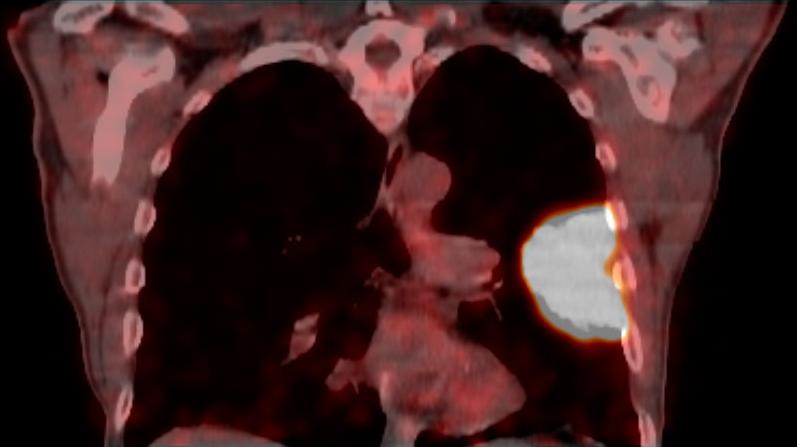

Lungenkrebs

Lungenkrebs befällt etwa 25 Prozent aller Krebskranken und gilt als häufigster Tumor beim Mann. Doch auch immer mehr Frauen sind betroffen. Die chirurgische Therapie ist für uns Mittel der Wahl, sofern keine Fernmetastasen vorhanden sind. Dabei können wir in unserer Klinik technisch hoch anspruchsvolle Lungenoperationen auf endoskopische Weise videoassistiert vorgenommen werden.

Mit dem Begriff "minimal-invasive Thoraxchirurgie" werden Schlüsselloch-Techniken für Operationen bezeichnet, in der Thoraxchirurgie eine noch junge Methode, die sich rasant entwickelt. In unserer Klinik kann diese schonende Technik sogar bei der Therapie von Lungenkrebs zum Einsatz kommen.

Technisch hoch anspruchsvolle Lungenoperationen können in unserer Klinik auf endoskopische Weise videoassistiert vorgenommen werden (VATS: Video-assistierte Thoraxchirurgie). Die bei konventionellen Lungenoperationen notwendige Eröffnung des Brustkorbs mit einem großen Schnitt und mit Auseinanderspreizen der Rippen entfällt bei der VATS-Lobektomie. Die Patienten erholen sich wegen der sehr viel geringeren Wunde („Operationstrauma“) sehr viel schneller. Auch sind die durch die Operation hervorgerufenen Schmerzen deutlich geringer. Bei einer anatomischen Operation mit Lungenteilentfernung müssen die „Versorgungsleitungen“ durchtrennt werden, dies sind die Blutgefäße und die Luftröhrenäste. Diese Operationsschritte und mehr können endoskopisch vorgenommen und über Video-Übertragung am Monitor mit Vergrößerung durchgeführt werden. Die Technik der VATS–Lobektomie/Lappen-Resektion wird bei Frühstadien des Lungenkrebses erfolgreich eingesetzt wie auch bei einer Vielzahl anderer anatomischer Lungenoperationen (Segmentresektionen).

Lungenmetastasen

Werden neben Lungenkrebs auch Lungenmetastasen diagnostiziert, stellt das die Medizin vor höchste Herausforderungen. Nur wenige Kliniken sind darauf spezialisiert, bei dieser Erkrankung chirurgisch einzugreifen. Durch besondere fachliche Expertise, einen großen Erfahrungsschatz und die technische Ausstattung ist unsere Klinik Ihr Ansprechpartner, wenn es um die chirurgische Therapie von Lungenmetastasen geht.

Laser-Chirurgie bei Lungenmetastasen

In unserer Klinik für Thoraxchirurgie werden zahlreiche Operationen an der Lunge mit dem modernen 1318NM-Diodenlaser durchgeführt. Das neue Gerät wurde speziell für die Lungenchirurgie entwickelt und hat besondere Eigenschaften, die das Schneiden von Lungengewebe ermöglichen: Mit dem Laser ist der Thoraxchirurg in der Lage, bluttrocken und übersichtlich durch das Lungengewebe zu schneiden. Dadurch können Metastasen und Tumoren, die tief im Lungengewebe liegen, onkologisch sicher entfernt werden. Anhand dieses modernen Verfahrens kann der Thoraxchirurg besonders gewebeschonend vorgehen und zahlreiche Lungenmetastasen entfernen, was mit konventionellen Methoden nicht möglich wäre. So kann die Prognose für den Patienten verbessert werden. Die sogenannte Laser-Metastasektomie ist eine etablierte chirurgische Behandlung, die bundesweit nur in großen Thoraxkliniken vorgenommen wird. Unsere Klinik ist die einzige in Ostwestfalen-Lippe, die Laser-Chirurgie bei Operationen der Lunge anbietet.